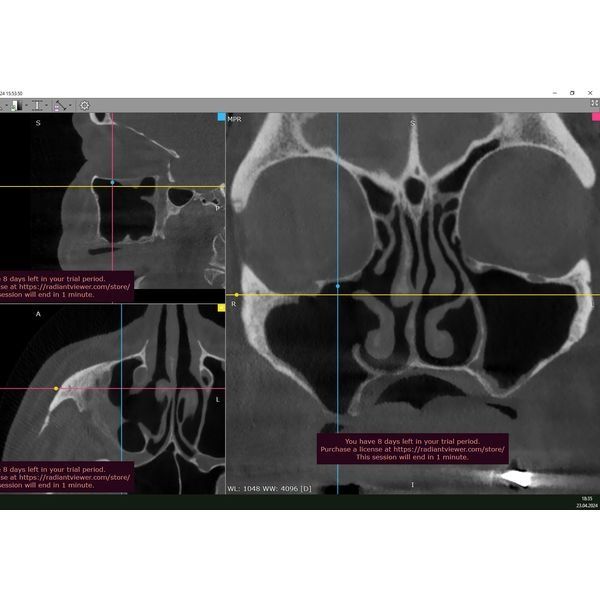

Была проведена конусно-лучевая томография головы. В ходе обследования определялись: обширный дефект мягких и твёрдых тканей верхней челюсти справа, тотальное затемнение верхнечелюстной пазухи (полное заполнение пазухи патологическим содержимым) с полипами и выделением содержимого в полость носа.

Через 6 месяцев после операции пациентке сделали КТ. По её результатам, воспаления верхнечелюстной пазухи и ороантрального сообщения больше не было.